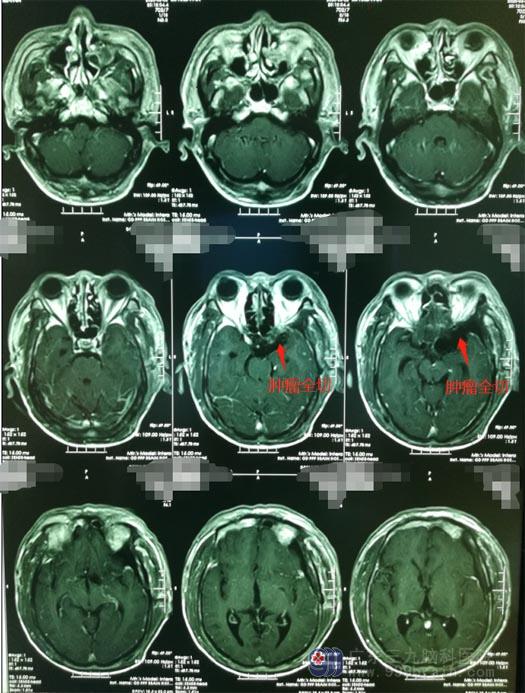

进一步左侧颈内动脉球囊闭塞实验提示:右侧颈内动脉未能完全代偿,这更加增添了手术难度和手术风险,术中需要避免损伤被肿瘤包绕的左侧颈内动脉。由医院副院长、神经外五科主任鲁明主刀“经左侧翼点入路行左侧蝶骨嵴内侧型脑膜瘤切除术”;术中见肿瘤包裹左侧颈内动脉、左侧大脑前动脉A1段、左侧大脑中动脉M1段;抽丝剥茧地自蝶骨嵴位置基底部将肿物从硬脑膜分离,在镜下保护好视神经和颈内动脉、大脑中动脉、大脑前动脉等大血管,将肿瘤一点一点地全部切除,视神经、动眼神经均保护完好,手术过程顺利。

术后次日,陈叔满意地告诉查房医生:眼睛看东西比之前清楚多了;他恢复得很好,没有出现偏瘫、失明等功能障碍及其它并发症。